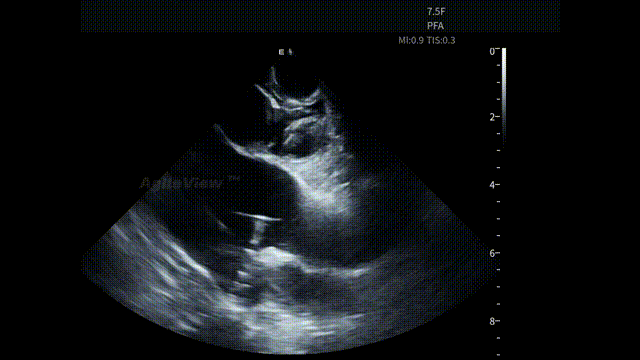

在PFA手术中,AgileView™ ICE 的PFA预设成像模式针对能量特点进行了优化,术中影像层次清晰、稳定性好,能够更直观地观察消融导管与心房组织的贴靠情况。这种“所见即判断”的影像反馈,对提升消融信心和术中决策效率非常有帮助。

“超清”PFA预设成像模式

匹配脉冲消融能量特性

针对 PFA 能量的物理特性,AgileView™ ICE 配备PFA专属预设成像模式,通过针对性的参数设置,使术中影像更贴合脉冲消融的操作需求,帮助术者更直观地观察导管与组织的贴靠情况,为术中判断提供稳定清晰影像支持。